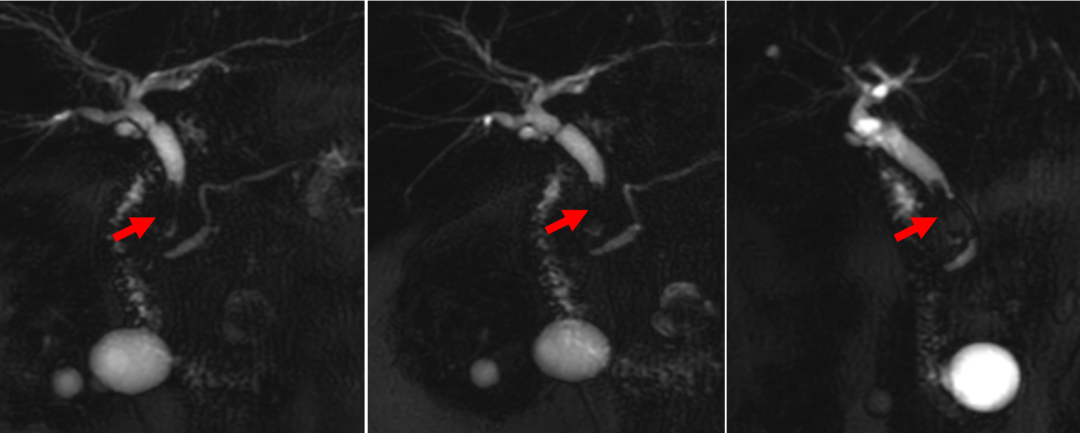

入院后 MRCP:胆总管中下段见一类圆形低信号结节影,大小约6mm*6mm*15mm

证实为 Hemolok 夹,2 粒,外围形成结石包裹

支持点 1:回看拔除T管之前CT影像

胆总管 T 管附近见短条状高密度影(疑似为hemolok夹)